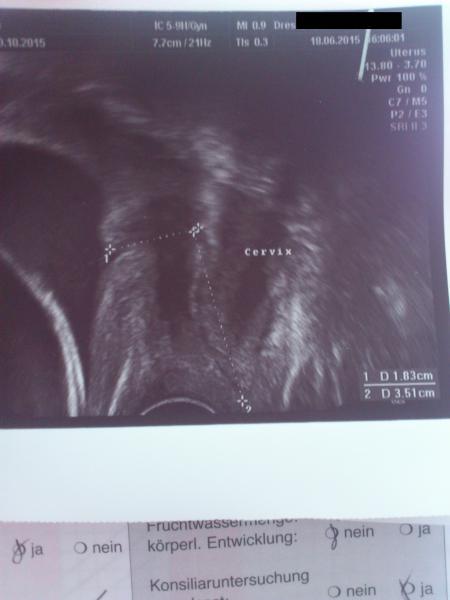

hallo ihr lieben...ich bin 24+0 ssw...gestern wurde mein gebärmutterhals gemessen.man sagte mir das dieser nach einer seite abknickt,was aber wohl kein problem darstellt.es wurden nun beide "linien" gemessen,also auch das stück, welches abknickt.im mutterpass stehen nun zwei werte, 1,8 für die linie ,welche nach rechts abgeht und 3,5 für die linie welche senkrecht nach oben führt.so war es auf dem ultraschall zu sehen.meine frage ist nun ob die beiden werte zusammengezogen werden und die summe dann die länge des gebärmutterhalses ergibt?man sagte mir das es sein kann das der knick auch noch verschwindet und der gebärmutterhals halbwegs gerade wird.meine frage an ist aber wie es sich mit den zwei werten verhält.ob diese addiert werden.vllt. ist es bei jemandem von euch ähnlich. vielen dank für eure antworten

hier mal ein bild vom ultraschall...so sieht es aus...diese krumme linie ist mein gebärmutterhals

Bild zu